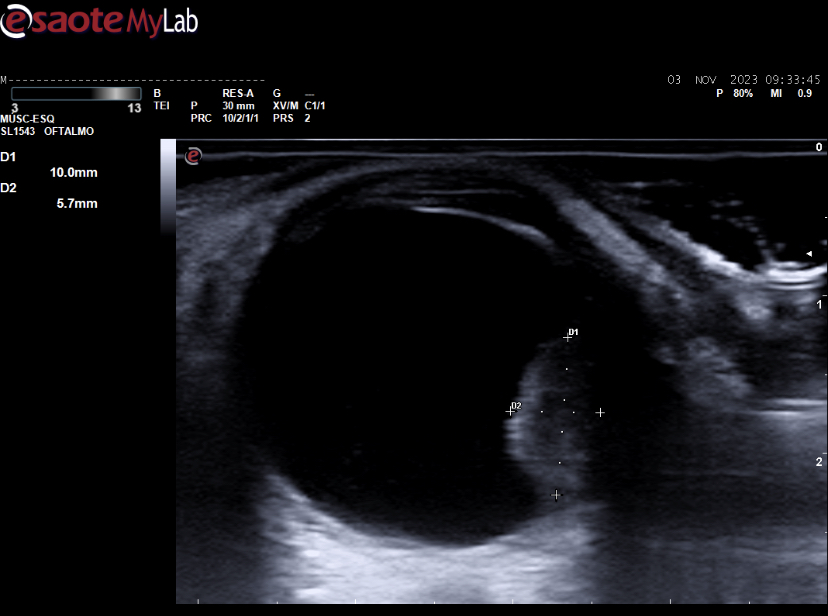

Ecografía ocular: lesión sólida polipoidea homogénea de 10*6 mm vascularizada junto a imagen de membranas hiperecoicas avasculares y móviles con los movimientos oculares en polo posterior.

Se deriva a urgencias oftálmicas hospitalarias donde corroboran nuestras imágenes con otra ecografía realizada por servicio de radiodiagnóstico y completan estudio con RMN: lesión coroidea hiperintensa en T1 e hipointensa en T2 de medidas basales de 16 mm por espesor de 6 mm con desprendimiento de retina posteroinferior y pequeño foco de hemorragia subretiniana posterior.